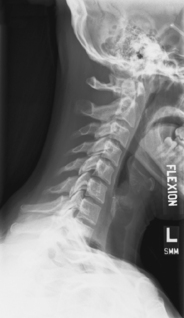

Lateral hyperflexion and hyperextension (S)

Hyperflexion and hyperextension critique